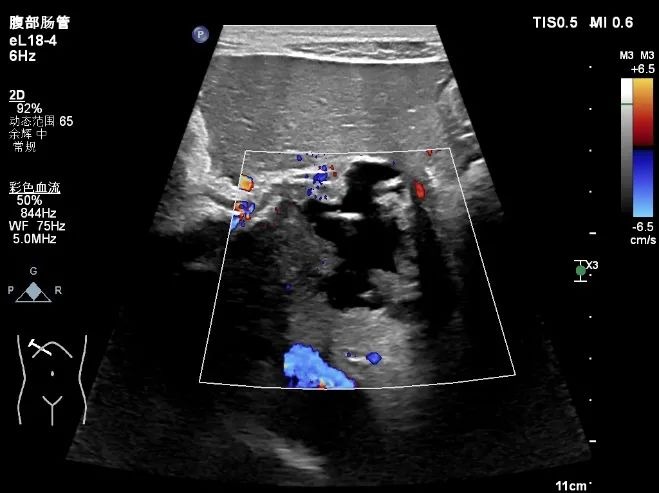

超声所示

肝脏体积增大,右叶斜径约 19.0cm ,肝内可见多个厚壁无回声,大的位于肝右叶,大小约 15.5cmx13.9cm 的囊实性结节,内可见粗大分隔及壁结节,肝内胆管未见扩张。CDFI: 囊肿周边可见少许血流信号(图 1-5 )。

图 3 CDFI: 囊肿周边可见少许血流信号